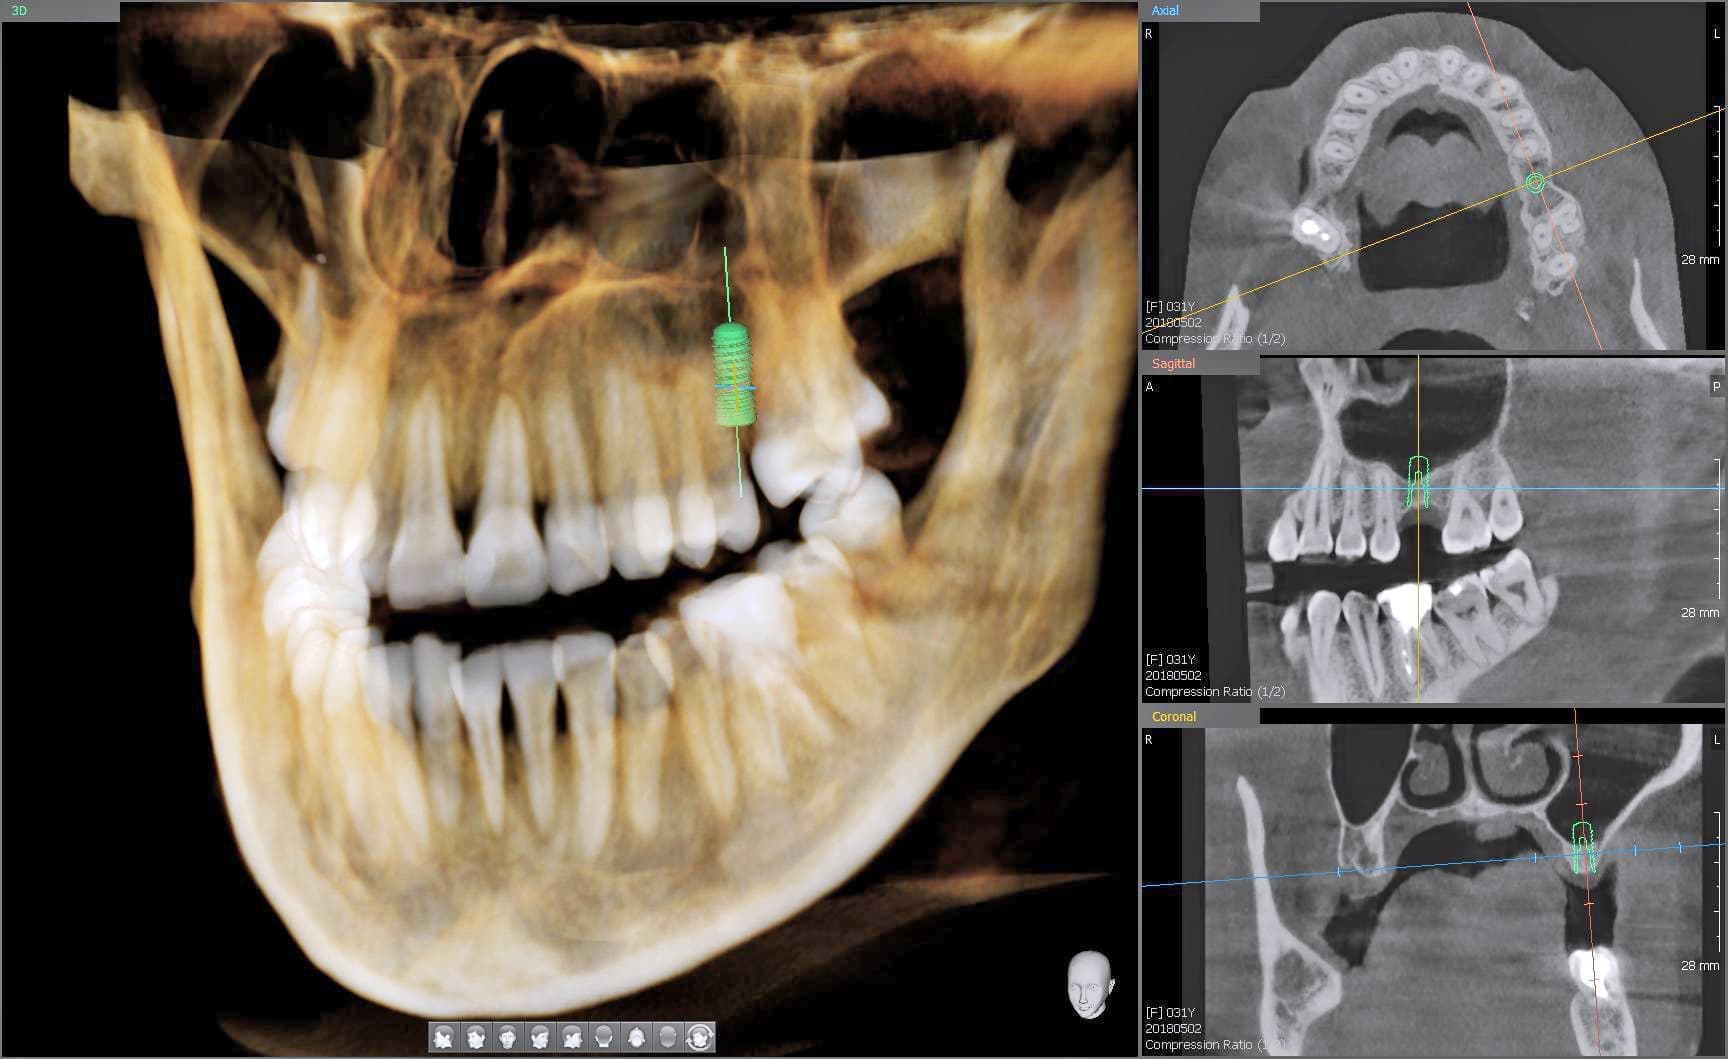

当院では、歯科用CT3Dデジタルレントゲンを活用し、身体への負担を少なく、状況を詳しく把握し、的確な治療を提供出来るよう心掛けております。

CTデジタルレントゲンに使われているX線センサーは高感度で照射時間も短く、より低線量でのレントゲン画像の取得が可能となり、お子様にも安心です。

インプラント手術や歯周病治療、歯の根の病気に関係する治療の正確な診断、治療計画には、CTによる撮影が欠かせません。

例えば、親知らずの抜歯や骨内に埋伏している過剰歯の抜歯等、正確な位置や神経や血管等との距離を3次元的に把握することで負担の少ない安心な処置が行えます。